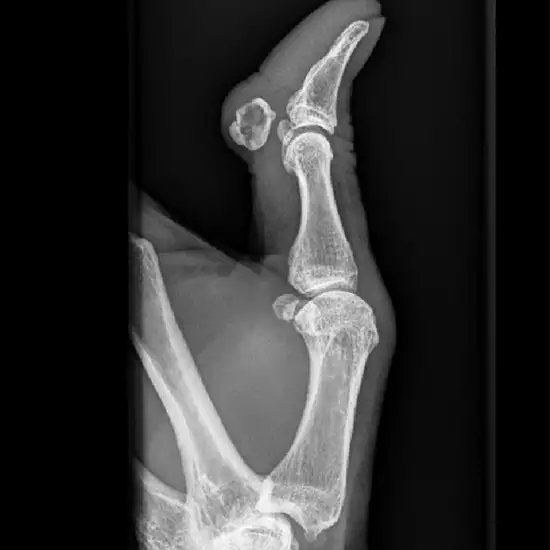

X-ray Left Thumb AP & LAT

An X-ray of the thumb is used to visualize the bones of the thumb and the surrounding soft tissues (skin and muscles).

• To identify any fractures of the thumb's bones and monitor the bone's healing once it has been set.

• To diagnose any suspected infection, osteoporosis, bone abnormalities or abnormal bone growth, and joint inflammation.